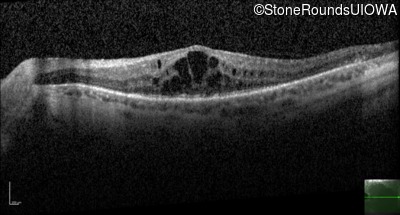

Age at visit: 46 years

This 46 year old man has had poor vision in dim light since age 2.

Diagnosis & molecular findings

AR Retinitis Pigmentosa SLC24A1 Met252 del2ggaAT Leu1052 del2ctTC AR